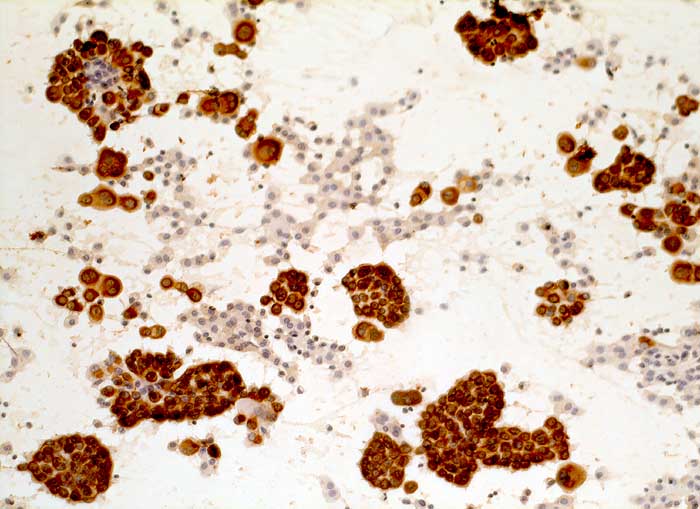

PathoPic – image database / PathoPic ID 5910 - malignes Pleuramesotheliom

malignes Pleuramesotheliom

Pleuraerguss Zytologie

Pleurapunktat: Die rundlichen und papilliformen Tumorzellverbände sind deutlich positiv für den Panzytokeratinmarker Lu-5. Makrophagen und Lymphozyten sind negativ.

Immunzytochemisch sind die im Vorbericht beschriebenen Tumorzellen eindeutig positiv für Lu-5, Calretinin und Vimentin, dagegen komplett negativ für Ber-EP4 und CEA. Diese Konstellation ist sehr typisch für ein malignes Pleuramesotheliom.

Zytologische Diagnose: Massenhaft Zellen eines malignen Tumors. Der Befund könnte unter anderem zu einem Mesotheliom passen.

Zytologie

Immunhistochemie

Lu5 Panzytokeratin

Vergrösserung

200